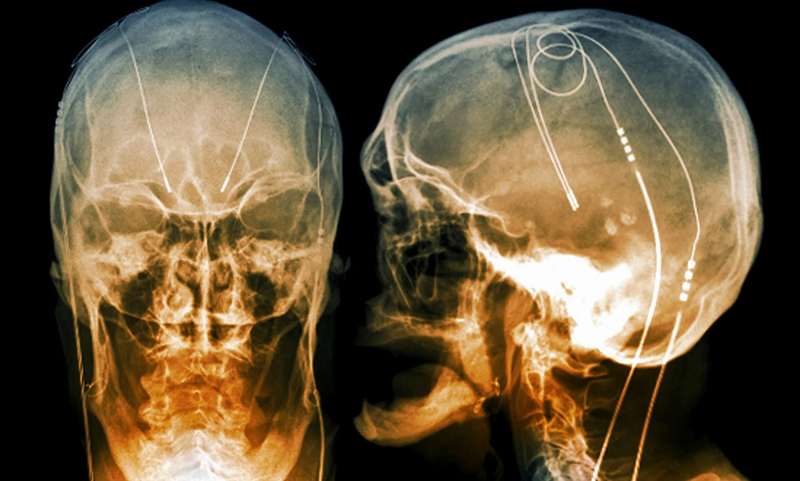

Eletrodos de estimulação cerebral profunda implantados na cabeça de um paciente com doença de Parkinson, uma espécie de “marca-passo cerebral (semelhante ao coração)”: radiografia colorida (fonte: Science)

Para tratar distúrbios do movimento causados ​​por distúrbios nos centros cerebrais, a estimulação elétrica de três zonas principais é usada: o núcleo intermediário ventral, a bola pálida interna e o núcleo subtalâmico (fonte: Health Plexus)

Na verdade, os médicos têm praticado exatamente esse efeito na forma de estimulação cerebral profunda (DBS) por meio de implantes neurais médicos, trabalhando com pacientes desde o final do século passado. Em primeiro lugar, com aqueles que sofrem de certos distúrbios da atividade cerebral, incluindo doença de Parkinson, transtorno obsessivo-compulsivo, epilepsia e assim por diante. Segundo especialistas da International Neuromodulation Society, em 2018 já existiam mais de 150 mil portadores desses implantes no mundo. Entre eles estão pessoas com lesões na medula espinhal, a quem os dispositivos DBS devolveram a oportunidade, que parecia perdida para sempre, de controlar pelo menos parcialmente seu próprio corpo.